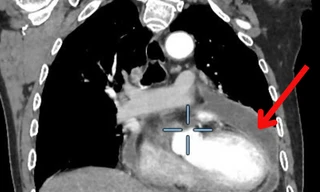

TPO - Nghĩ rằng chỉ bị cảm sốt thông thường, cụ ông N.V.G. (82 tuổi, ngụ tại Long An) không ngờ bản thân đang đối mặt với một trong những thể lao ngoài phổi nguy hiểm nhất – lao màng ngoài tim, có thể gây tràn dịch màng tim, suy tim, đe dọa tính mạng nếu không được can thiệp kịp thời.